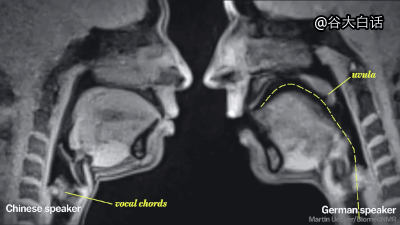

#爱你爱到骨头里#【MRI下诡异而奇妙的人体】这是一段用核磁共振成像技术制作的动态短片,将人类喝水、亲嘴、嘿咻、拉翔、生娃、说中文、说德文等日常活动展现得毫纤毕现、一览无遗。doge微猎奇,微暴,慎点。